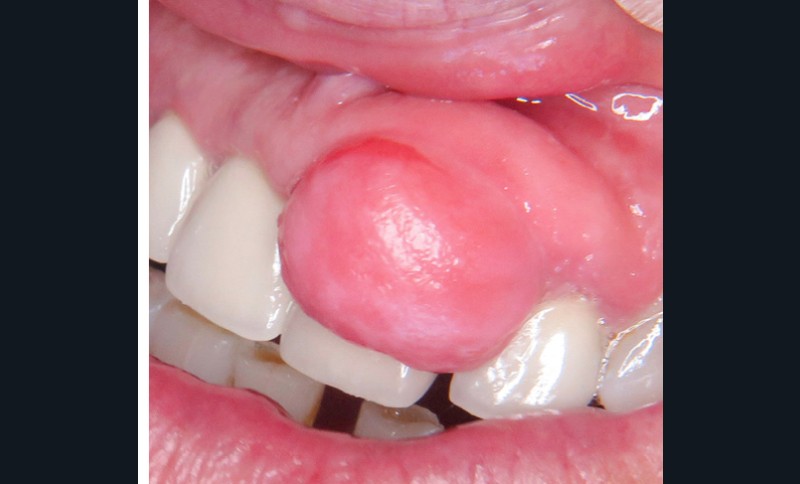

2. Épulis fibreux

- Nodule ferme, muqueuse de couleur normale (fig. 2a et b).